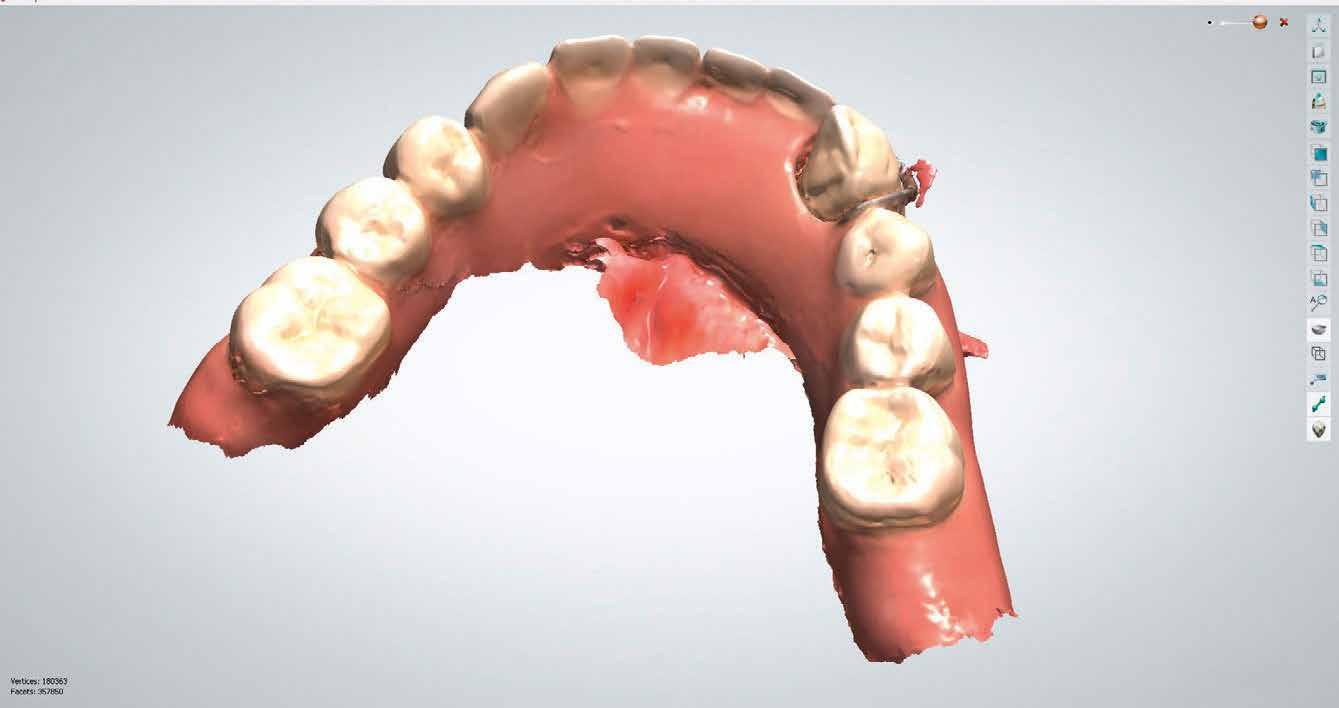

1. kép: Preoperatív szituáció.

Kedvezőtlen fogállás, vagy aszimmetrikus lágyszöveti kép jelentősen megnehezíti a frontfog-rekonstrukció amúgy sem könnyű elkészítését. A forma és szín harmonikus integrációján kívül a lágyszövet formája döntő jelentőségű a természetes hatás szempontjából. Sok esetben szükséges ideiglenest készíteni, amivel a kezelőcsapat megfelelhet a gingiva biológiájának.

Pácienseset

33 éves páciens konzultált a rendelőben 3 évig tartó fogszabályozása elemeinek eltávolításáról szájából. A kárieszek eltüntetésén kívül optimalizálni szerette volna esztétikai kinézetét. Az első esztétikai elemzés a frontfogak kedvezőtlen hossz-szélesség arányát mutatta (1. kép). A bal felső szemfogat a pulpa elhalása következtében endodonciai kezelésnek is alá kellett vetni.

Tervezés

A terv a felső front rekonstrukciója volt. Anyagválasztás oldaláról figyelembe kellett venni, hogy a páciens szokásszerűen, rendszeresen fogyaszt kemény diót, ráadásul éjszaka csikorgatja a fogát (bruxizmus), és gyakran szorítja öszsze állkapcsát. A frontkoronáknak tehát esztétikus kinézet, funkcionalitás mellett kiemelkedő szakítószilárdságúnak és

nagyon erősnek kell lenniük. Hat teljes kerámiakoronával kívántuk megoldani a hossz és szélesség aránya (a fogak meghosszabbításával), és az aszimmetrikus gingivavonal optimalizálását.

Klinikai kezelés

A gyökérkezelést és a kárieszek megszűntetését követően kompozittömések készültek, majd preparálták a restaurálandó frontfogakat (3. kép). Ideiglenes koronák is szájba kerültek (4. kép), a jobb kismetszőt meghosszabbították. A fogínylefutás szimmetriáját az ideiglenes koronák megtámasztása segítette. A fogak és íny kívánt szimmetriáját elérve véglegesítették a preparációt (5. kép) és elkészültek a lenyomatok.